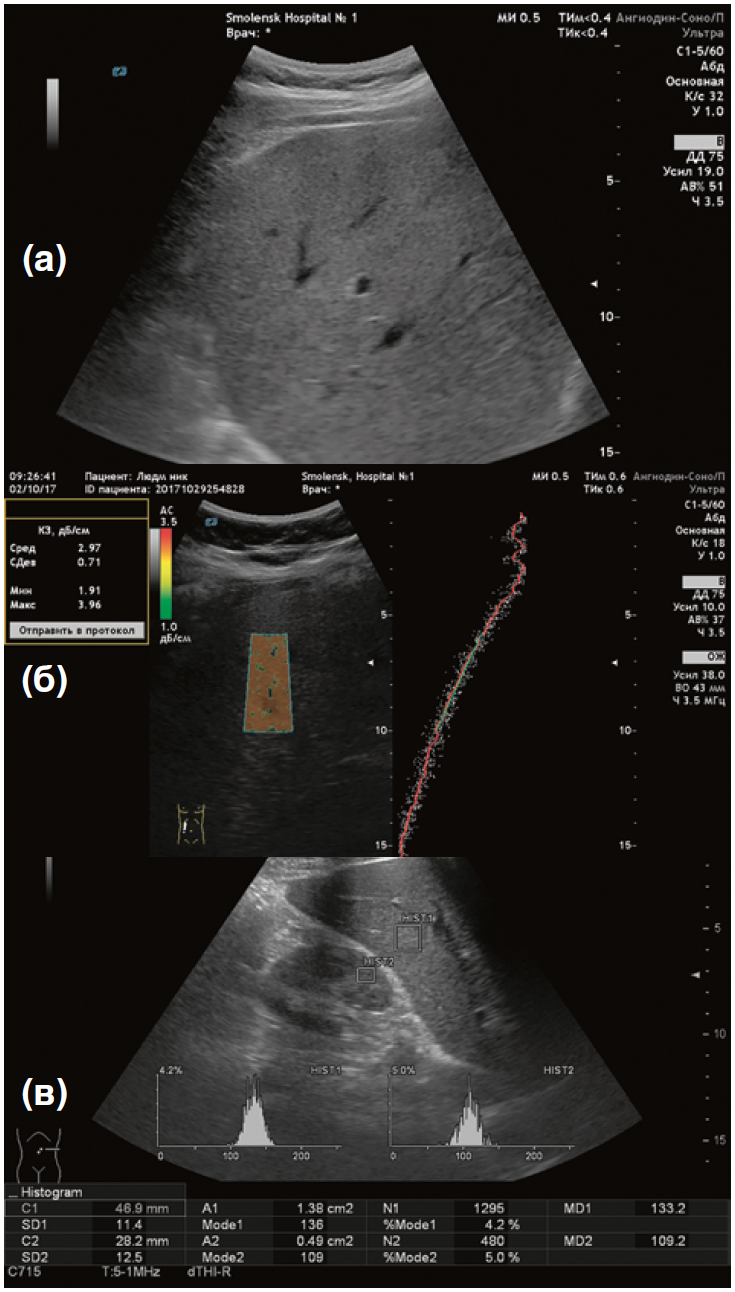

7-й этап. Ультразвуковая стеатометрия печени на аппарате «БИОСС Ангиодин Соно-П/Ультра» (Россия) с визуальной и количественной оценкой коэффициента затухания ультразвуковой волны (дБ/см) (рис. 1).

Рис. 1. Методика проведения ультразвуковой стеатометрии

Примечание. 1 — печень, 2 — активная зона измерения, 3 — количественный показатель стеатометрии (коэффициент затухания ультразвуковой волны).

Рис. 2. Ультразвуковое исследование печени в мультипараметрическом режиме

Примечание. (а) — ультразвуковое исследование печени в В-режиме (увеличение органа в размере, эхогенность повышена, звукопроводимость снижена, мелкие и средние сосуды не визуализируются). (б) — ультразвуковое определение гепаторенального индекса (ГРИ 0,84). (в) — ультразвуковая стеатометрия (коэффициент затухания ультразвуковой волны 3,37 дБ/см).